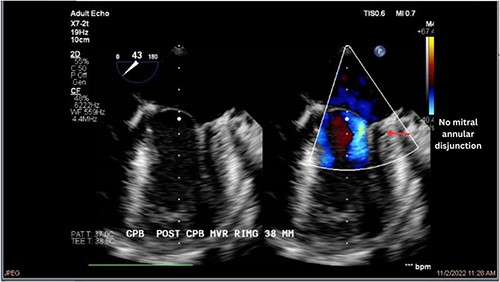

Both sisters underwent a minimally invasive procedure through a right-sided lateral minithoracotomy performed at the level of the third or fourth intercostal spaces. Cardiopulmonary bypass was established through a femoral access and cardioplegic cardiac arrest was achieved through a modified Del Nido solution (20 ml/kg). Mitral valve repair was performed through isolated annuloplasty using in both cases a 38-mm semi-rigid annuloplasty ring. Transesophageal echocardiography after repair revealed excellent surgical results, with no rest regurgitation, no SAM of the mitral valve and most importantly no detectable mitral annular disjunction (Figs 7 and 8). In both cases, being performed several months apart, the patients were extubated in the operating room and transferred to our ICU for further observation.